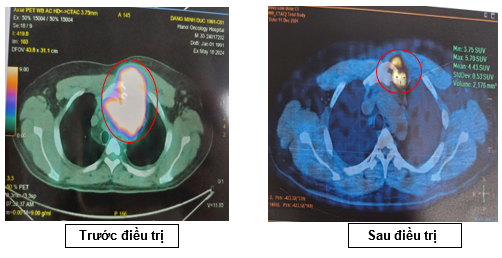

-         Kết quả chụp PET/CT sau điều trị 6 đợt (tháng 12/2024)

+       Không thấy hạch nền cổ và thượng đòn 2 bên

+       Hình ảnh amydal phải tăng nhẹ kích thước tăng hấp thu FDG (SUVmax: 4,3), dày trần vòm và hố Rosenmuller 2 bên, tăng hấp thu FDG (SUVmax: 6,5)

+       Hạch trung thất nhóm 3A, kích thước 9x11mm, tăng hấp thu FDG (SUV max 4,3)

+       Hình ảnh hủy xương ở cán xương ức lệch trái, xâm lấn phần mềm xung quanh, tăng hấp thụ FDG (SUVmax: 5,8)

+       Hình ảnh tuyến ức kích thước 18x57x45 mm, tăng chuyển hóa glucose không đều, cần theo dõi thêm

Nhận xét: Sau 06 chu kỳ điều trị, khối trước xương ức giảm kích thước (từ 109x90mm còn 57x45 mm, trước điều trị SUVmax: 17,88 -> sau điều trị SUVmax 5,79). Hạch cổ, hạch thượng đòn, hạch bẹn, hạch rốn gan không còn nhìn thấy trên phim PET/CT, không tăng chuyển hoá FDG -> PET/CT sau 6 chu kỳ hóa trị: Đáp ứng một phần (PR) theo tiêu chuẩn Lugano 2014.

Trường hợp bệnh nhân nam 33 tuổi, được chẩn đoán U lympho Hodgkin típ hỗn hợp tế bào giai đoạn IVAE với tổn thương ngoài hạch tại xương ức. Sau 6 chu kỳ hóa trị ABVD, bệnh nhân đạt đáp ứng một phần cả về lâm sàng và hình ảnh. PET/CT cho thấy giảm kích thước và mức độ chuyển hóa FDG của các tổn thương, phù hợp với đánh giá PR theo tiêu chuẩn Lugano 2014.